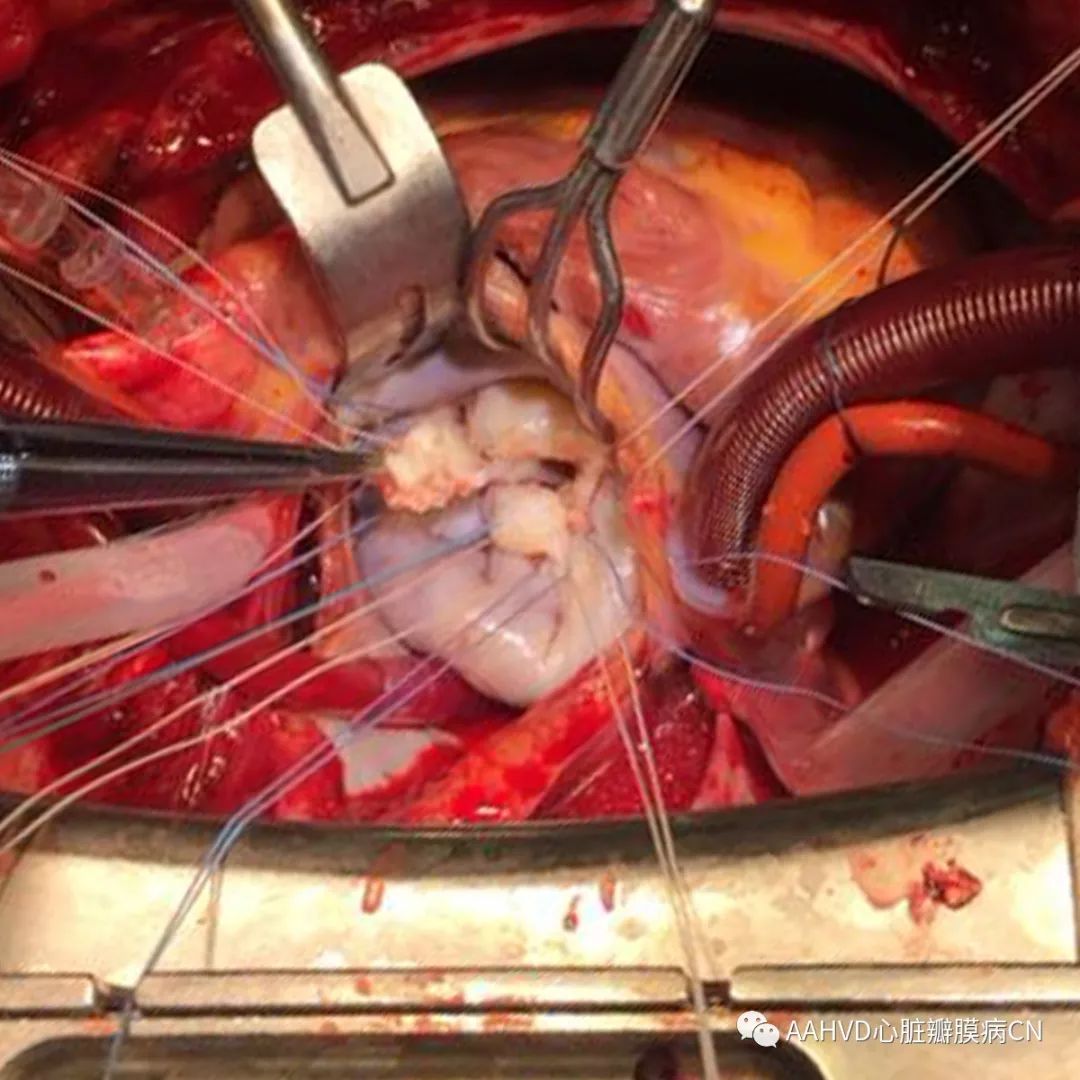

术中情况:

640_3640_4

二尖瓣前后叶瓣尖增厚、钙化、粘连,二尖瓣瓣下腱索挛缩,前叶可见一团块增生物